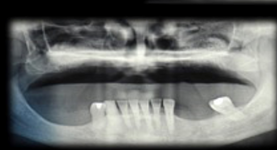

The aim of this workshop was to assess the posterior maxillary area. The posterior maxilla naturally presents low-height alveolar process, which is anatomically limited by the maxillary sinus. The roots of the molars are closely related to the floor of the maxillary sinus. In the center of the alveolar crest we find the root trifurcation area, which is the ideal site for implant placement from a prosthetic perspective, and where there is the lowest bone height in the sinus floor. This means that placing implants of standard dimensions after tooth loss

in this area is limited.

The resorption processes resulting from such loss, common to all regions of the alveolar process, may aggravate this situation. Maxillary sinus pneumatization, on account of increased osteoclastic activity along the sinus membrane and the absence of a dental “barrier” facing changes in sinus air pressure, may affect the morphology of the site. These conditions pose an anatomical challenge to the treatment of the edentulous posterior maxilla using dental implants. The techniques to repair defects in the residual alveolar ridge with autologous bone graft procedures have predictable results, which are described in the literature. A factor that explains their good results is that there are no immune reactions that may interfere with the process of tissue remodeling and development. They intrinsically have osteoblasts and growth factors responsible for the cellular changes that occur after implantation, and that end with remodeling and bone formation at the site1. Its disadvantage is the need for an additional donor surgical area which can be intraoral, in cases in which the need for reconstruction is small, or extraoral in cases of medium-sized or large reconstructions. In the 1980s, bone grafting techniques in the maxillary sinus were used to solve the problem of lack of bone, and to allow for implant placement. One of the techniques described is surgery to lift the floor of the maxillary sinus, known by its name in English: Sinus Lift2,3.

Use of short implants.

Question No. 1. Short implants or maxillary sinus lift? Which technique is more predictable according to the literature? According to the literature studied, the maxillary sinus lift technique is better documented, showing long-term implant survival rates. However, there are possible complications, such as: sinusitis (3%) and infections (1%), in addition to a higher morbidity. This makes it relevant to evaluate other techniques, which show similar results5. Currently, the use of short implants (less than 8 mm) is a practice that in the last six years (medium term) has acquired sufficient scientific support to be applied, depending on the clinical situation6,7,8.

Question No. 3. Indications and factors to consider to perform a lateral approach maxillary sinus lift. Indicated in the absence of sufficient alveolar bone for implant placement with predictability in the maxillary sinus. The techniques for such a procedure would be:

Question No. 5. Crestal approach or lateral window approach in the sinus lift technique? There is no antagonism. On the contrary, both techniques have excellent results and are complementary. Implant survival rate is similar.